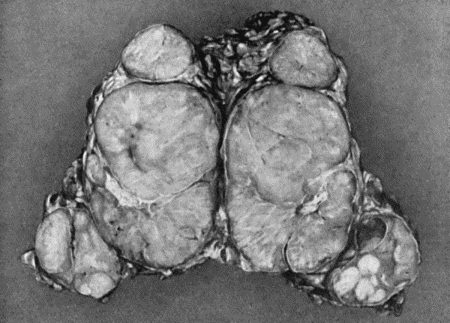

78.Mass of Tuberculous Glands removed from Axilla 333

79.Tuberculous Axillary Glands 335